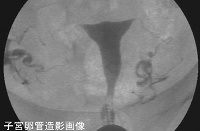

妊娠成立は大きく分けると次のようになります。

2.捕捉(排卵した卵子を卵管采に取り込む)

3.受精(卵管内での受精)